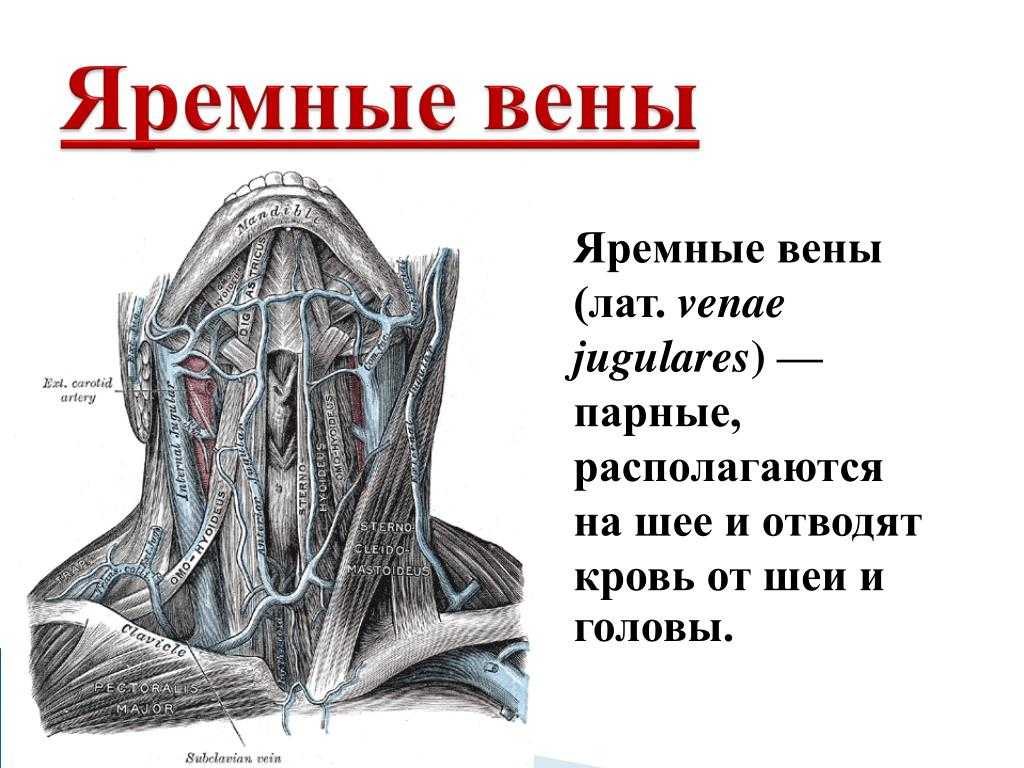

Анатомия внутренней яремной вены: КТ изображения